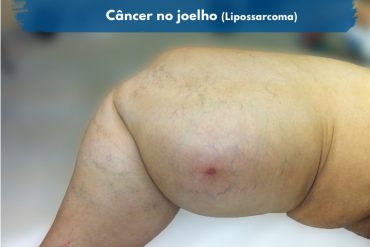

- Lipossarcoma.

Câncer no joelho fotos